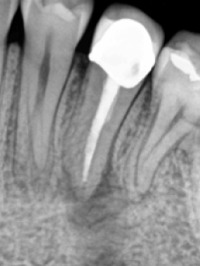

Fig 3a. Periapical radiograph of tooth #20. There is an associated radiolucency at the apex of this root-filled tooth. (1)

Fig 3b. Coronal CBCT slice of the same tooth revealing a missed buccal canal and an associated apical radiolucency. (1)